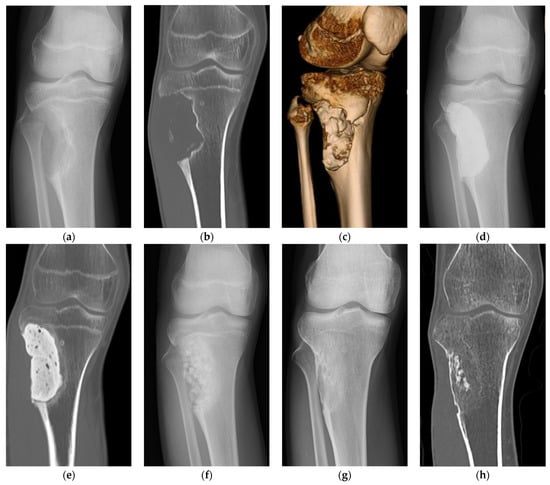

- Tamai, N.; Myoui, A.; Tomita, T.; Nakase, T.; Tanaka, J.; Ochi, T.; Yoshikawa, H. Novel hydroxyapatite ceramics with an interconnective porous structure exhibit superior osteoconduction in vivo. J. Biomed. Mater. Res. 2002, 59, 110–117. [Google Scholar] [CrossRef]